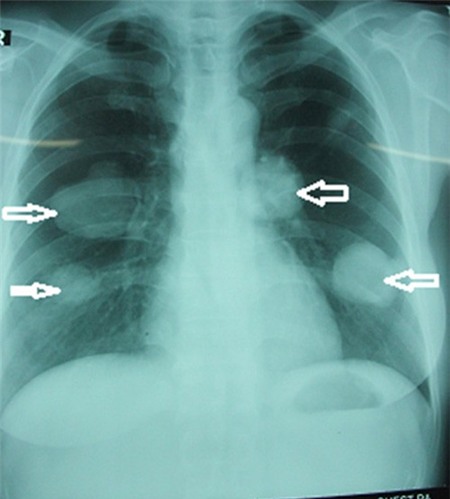

Lần đầu tiên VN phát hiện hai bệnh nhân bị sán chó. Hãi hùng hơn đây là những khối u lớn, hàng nghìn đầu sán ngoe nguẩy trong phổi người “chực chờ” vỡ.